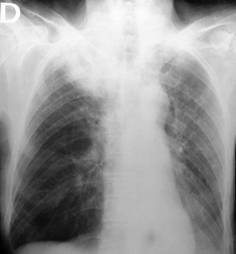

Fig. 72 Cancer pulmonar periferic

Nu prezinta simptomatologie clinica la inceputul evolutiei si este descoperit intamplator cu ocazia unui examen de rutina. Radiologic, apare ca o opacitate de forma rotunda, marime variabila cu diametrul intre 2-6 cm situat in plin parenchim pulmonar, la distanta de hil.

Imaginea radiologica seamana cu un chist hidatic de care se deosebeste prin aceea ca intensitatea este mai mare si conturul mai net. In hil si mediastin ganglionii sunt mariti (realizeaza imagine de complex bipolar). In cursul dezvoltarii, tumora poate avea aspect usor polilobat sau ombilicat.

Ombilicarea tumorii constituie semnul lui RIGLER care reprezinta un focar de necroza sau de scleroza la periferia tumorii. De asemenea, din periferia tumorii apar in evolutie mici prelungiri (spiculi) spre parenchim. Cancerul solitar se escaveaza frecvent. O varietate a cancerului periferic este cancerul varfului pulmonar descris de PANCOAST si TOBIAS in care tumora are tendinta la dezvoltare pleuro-parietala in zona sulcusului, cu invazia si distrugerea arcului posterior al coastei 1 si 2 sau apofizelor transverse ale vertebrelor T1-T2; se insoteste de simptome neurologice caracteristice (din partea plexului brahial, dureri si paralizie a membrului supertior) si tulburari ale simpaticului cervical (sindromul Claude -Bernard-Horner).